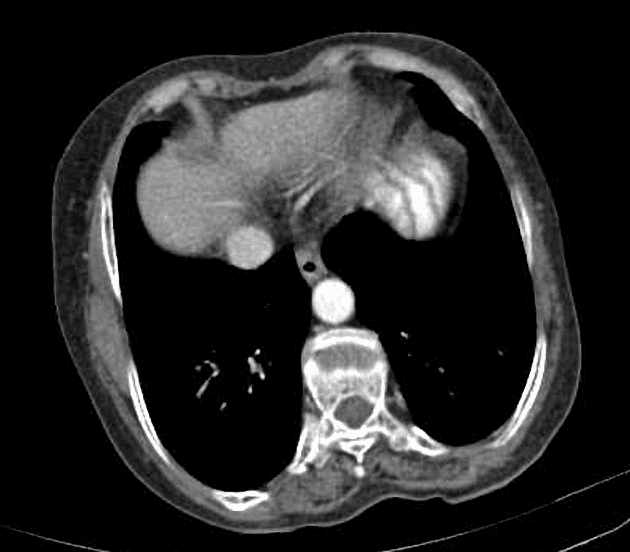

Long cystic duct remnant with choledocholithiasis after cholecystectomy

Các đợt sốt và đau bụng cấp tính tái diễn. Tiền sử phẫu thuật cắt túi mật sáu năm trước do viêm túi mật cấp tính.

MRCP cho thấy mỏm ống túi mật dài chạy song song với ống gan chung và hợp lưu ngay phía trên đầu tụy. Nhiều hình khuyết trong lòng tại vị trí nối với mỏm ống túi mật và dọc theo đoạn xa ống mật chủ. Giãn nhẹ đường mật trong gan phía thượng lưu, rõ rệt hơn ở thùy gan trái. Thảo luận: Mỏm ống túi mật dài là một biến thể giải phẫu sau phẫu thuật đã được ghi nhận sau phẫu thuật cắt túi mật và có thể tạo điều kiện thuận lợi cho việc hình thành sỏi mật tái phát và viêm đường mật. Chiều dài mỏm lớn hơn 1 cm được coi là có ý nghĩa lâm sàng, đặc biệt khi kết hợp với vị trí cắm thấp của ống túi mật và đường đi song song với ống gan chung, như có thể thấy trên MRCP. Cấu trúc như vậy có thể đóng vai trò là ổ đọng gây ứ mật và hình thành sỏi, đồng thời có thể giả dạng sỏi sót hoặc các biến chứng đường mật sau mổ khác. Do đó, việc nhận diện chính xác là rất quan trọng để tránh diễn giải sai và chẩn đoán chậm trễ. MRCP cung cấp một đánh giá không xâm lấn và có độ chính xác cao về giải phẫu đường mật sau phẫu thuật, cho phép mô tả rõ ràng mỏm ống túi mật, vị trí cắm và các hình khuyết trong lòng đi kèm. Ở những bệnh nhân có các triệu chứng đường mật tái phát sau phẫu thuật cắt túi mật, MRCP là phương pháp chẩn đoán hình ảnh được lựa chọn hàng đầu để hướng dẫn xử trí phù hợp, bao gồm can thiệp nội soi hoặc phẫu thuật.

Mỏm ống túi mật dài kèm sỏi ống mật chủ sau phẫu thuật cắt túi mật